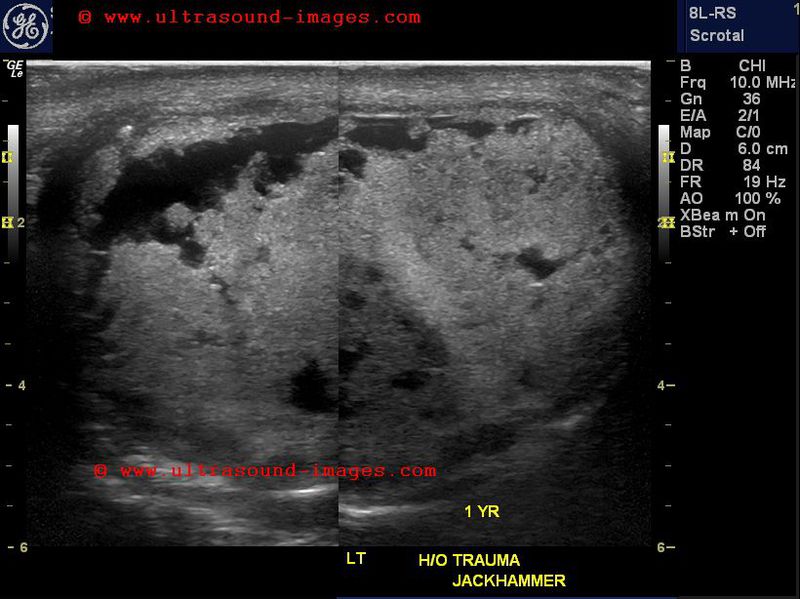

Ruptured-testis-case-4

This middle aged male had traumatic injury to the left testis from a jackhammer more than a year ago. This old severe injury to the testis is seen as multiple areas of rupture of the tunica albuginea of the left testis with multiple areas of necrosis within the testis. The normal right testis is shown for comparison. Color Doppler ultrasound reveals lack of flow in the injured testis suggesting that this left testis is non viable and cannot be saved. The large size of the left testis further confirms the severity of the injury with resultant fluid collection and edema of the affected testis.